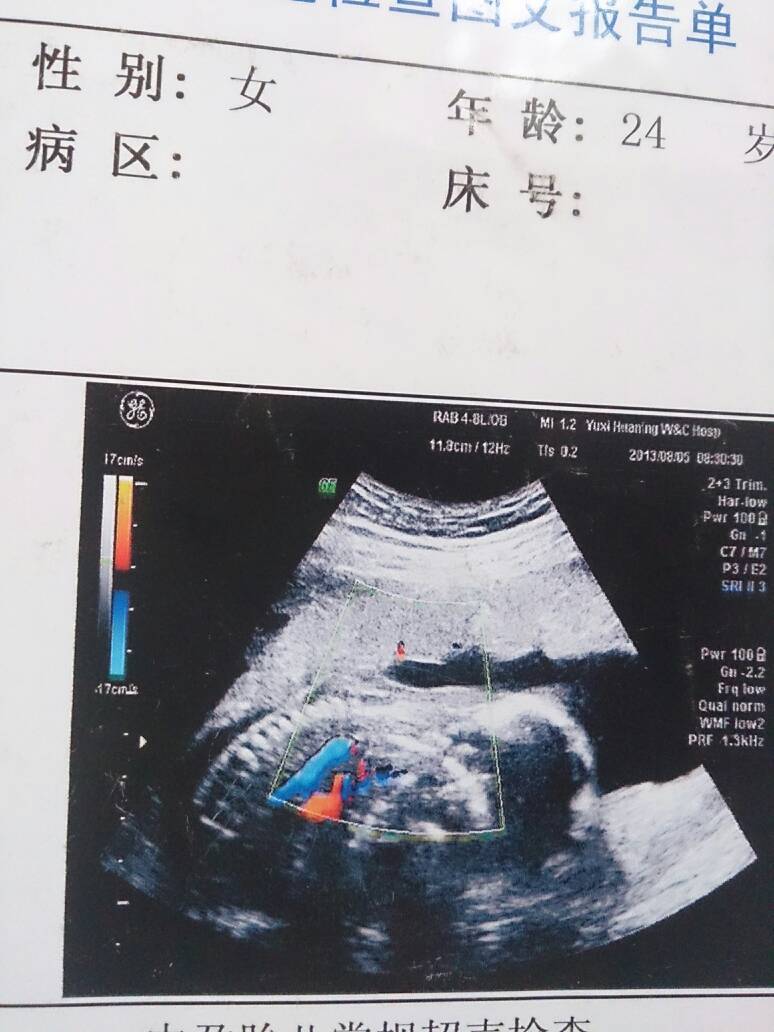

谁会看b超单上有蓝色和橘黄色代表什么呢,图上显示胎儿的什么部分 点击展开 匿名用户 2013-08-22 11:29 满意回答 那是心脏的、动脉和静脉、能看看数据吗? 匿名用户 2013-08-22 12:14 宝宝知道提示您:回答为网友贡献,仅供参考。 为您推荐: 其他回答 问医生吧?我上次陪朋友去照 看的照片没这个的啊 ,全都是黑白的 匿名用户 2013-08-22 11:43 相关问题 乐嘉性格色彩测试求解~~(感觉好奇怪的结果) 红色:11;蓝色:11;黄色2;绿色:7 乙炔尿酸检测剂测男女准吗!黄色不变色都是女孩!绿色蓝色是男孩